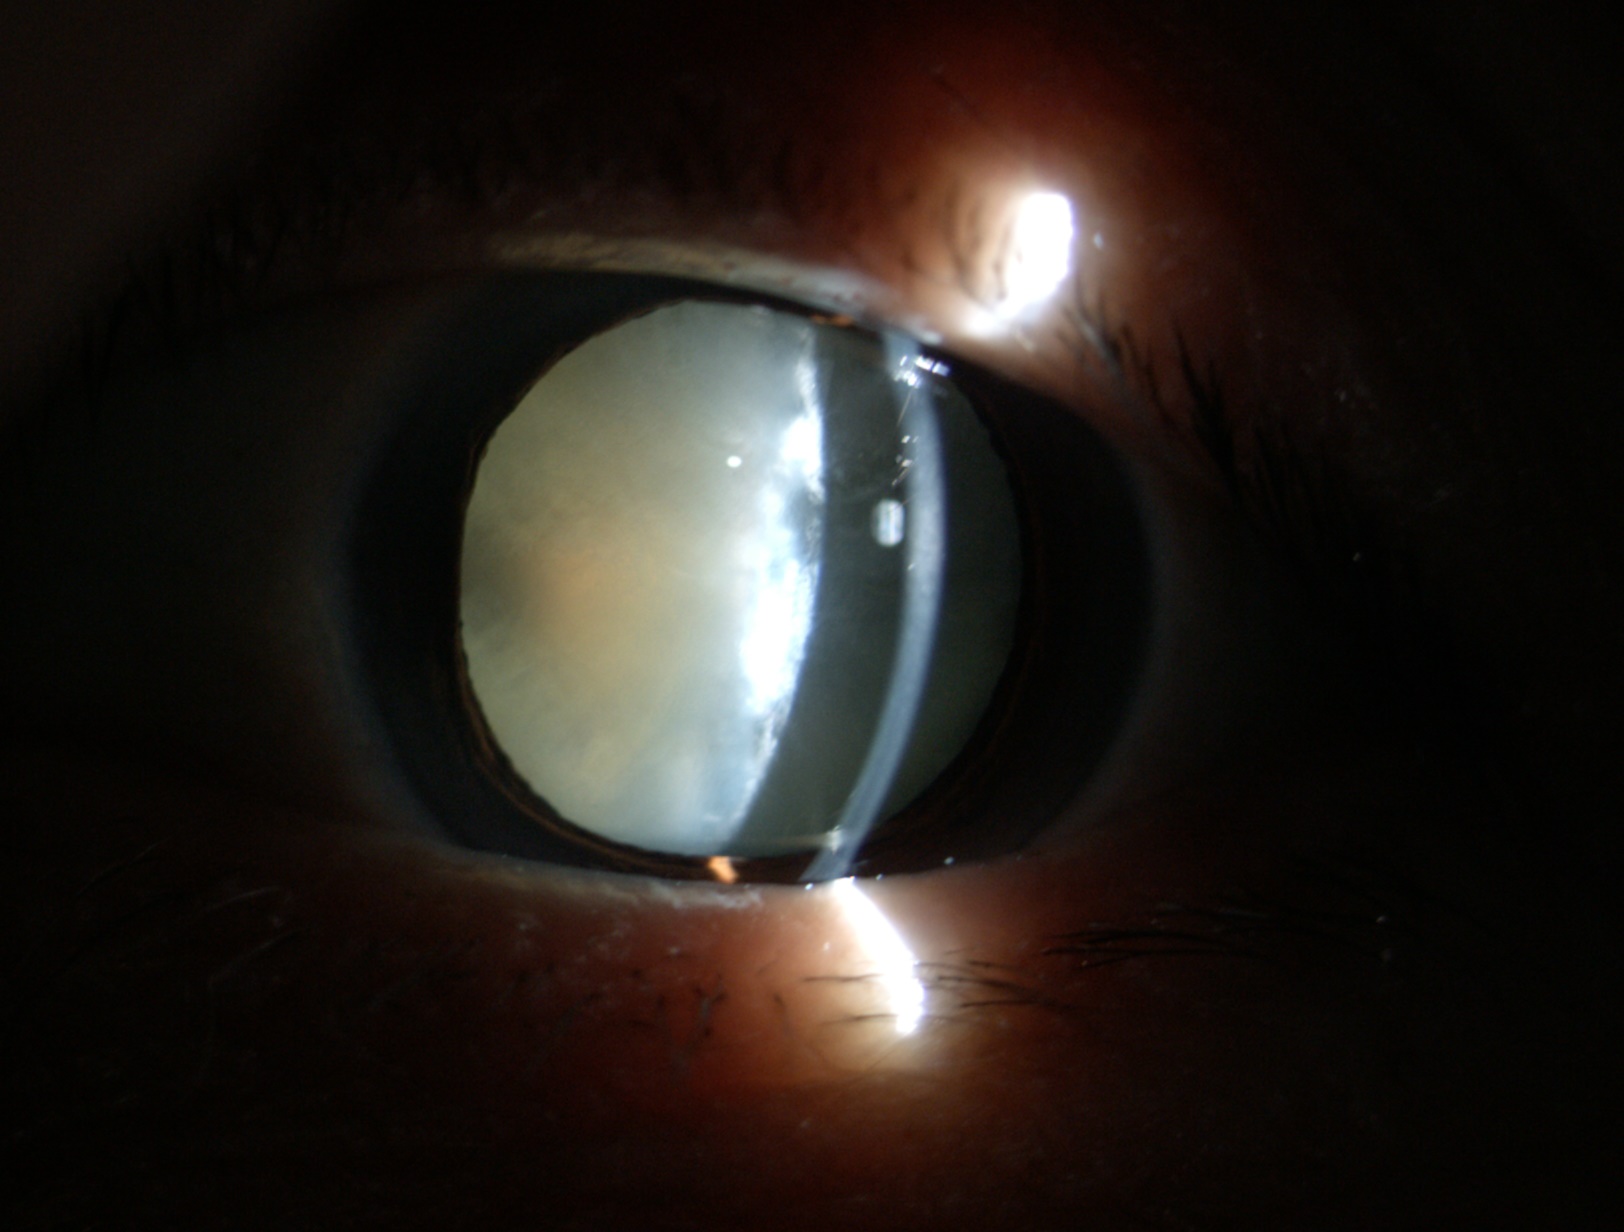

老年性白內(nèi)障

夏季強(qiáng)烈的陽(yáng)光通常使瞳孔變小,此時(shí)往往視力下降更明顯,適合手術(shù)者更應(yīng)當(dāng)機(jī)立斷。